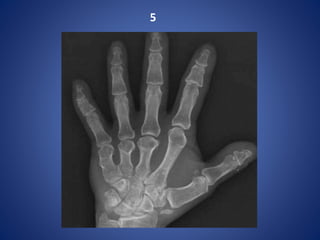

Proximal row carpectomy for scaphoid non-union

Proximal row carpectomyfor scaphoid non-union